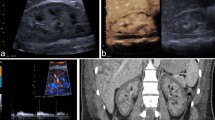

Using reference information from anatomic axial and coronal T2-weighted images and post-contrast T1 images, the slice with the maximum diameter of the tumor was selected in the ImageJ software (National Institutes of Health, Bethesda, MD). Three radiologists (Z.S., F.D., Y.S., all board-certified radiologists engaged in abdominal imaging for 8, 10, 9 years, respectively) outlined ROIs around the edges of the tumors on the DCE-MRI map (Fig. 1a). Parameter outlines covered the whole tumor as much as possible and excluded pulsatile artifacts from blood vessels and susceptibility artifacts from adjacent bowels. Then the same ROI was copied to parametric maps (Fig. 1b,c).

Commonly, values of Ktrans greater than 1.2 min−1 are considered pseudo-permeability in large blood vessels or errors in fitting36,37; therefore any pixels with Ktrans larger than 1.2 min−1 or with Ve beyond the range of 0–100% were excluded from parametric maps. Based on this situation, histogram function in ImageJ was utilized and threshold value of kinetic parameters were set respectively such as Ktrans (0, 1.2 min−1), and Ve (0, 1). Then the traditional Mean values of Ktrans, and Ve and heterogeneity analysis (i.e., Mode, Skewness, and Kurtosis) were automatically calculated. Kurtosis described how sharply peaked a histogram was compared with the histogram of a normal distribution. Accordingly, whereas a normal distribution had a Kurtosis of 0, a more peaked histogram had a positive Kurtosis value. Skewness described the degree of asymmetry of a histogram: a perfectly symmetric histogram had a Skewness of 0, a histogram with a long right tail had a positive Skewness, whereas a negative Skewness was due to the presence of a long left tail. The histogram graphs were plotted with the parametric values on the x-axis with a bin size of 0.024 min−1 for Ktrans, and 0.02 for Ve (with a bin number of 50) (Fig. 2a,b).